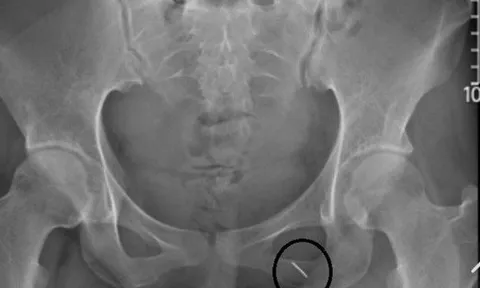

Phòng thượng mã phong cho chú rể, cô dâu bị kim đâm xuyên mông

Chiếc kim gài gấu váy cưới được các cụ mách cho cô dâu cứu chồng đêm tân hôn nếu không may bị thượng mã phong đã khiến cô dâu phải đến viện ngay đêm tân hôn